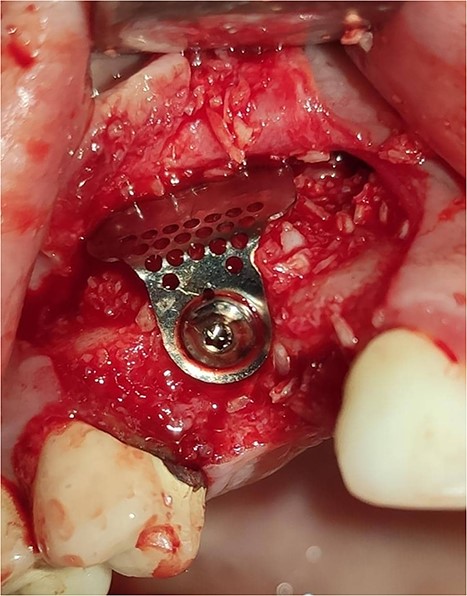

Under local anesthesia with 4% articaine solution, a full-thickness flap was raised to expose the alveolar ridge. The initial point was marked with a point drill. The implant site was first prepared with a 2.2 mm pilot drill, and then with a 3.3 mm drill. After preparing the implant bed, we noticed the disappearance of the coronal and middle third of the buccal wall, exactly as planned. A submerged implant system (INNO submerged implant; Cowellmedi Inc, South Korea) was inserted according to the manufacturer’s instructions (Fig. 1). The insertion torque value was 33 N.cm. several perforations were prepared at the buccal side of the recipient bone bed using a small round bur for better blood supply. An allogeneic bone graft material (Cortical Cancellous powder; TRCIR Co, Iran) was used to reconstruct the buccal plate. A prefabricated L-shaped titanium mesh has been adapted to fit the shape of the alveolar ridge to be reconstructed, and it was fixed to the implant with a cover screw (Fig. 2). The flap was mobilized to permit a tension-free primary closure, was closed with 4–0 silk sutures. Sutures removal was done after 1 week. The surgical sites were left to heal for 6 months.

Inserting a dental implant of 3.5 mm diameter and 10 mm length into its prepared bed. The implant was completely surrounded by bone in its apical third only.

Reconstruction of the buccal plate using an allogeneic bone graft material and a prefabricated L-shaped titanium mesh. The titanium mesh was fixed to the implant with a cover screw.